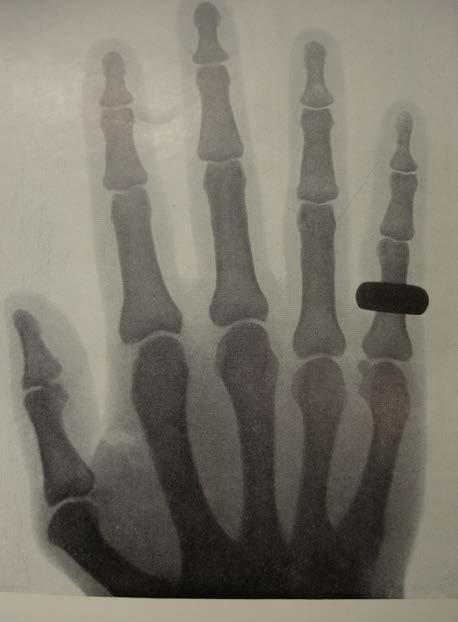

Medicinsk billeddannelse - stiller skarpt på din sygdom og behandling

Sundhedssektoren er forbruger af noget af den mest avancerede højteknologi til diagnostik, monitorering og behandling ikke mindst i forbindelse med patientspecifikke forløb. Samtidig er markedet for sundhedsteknologi globalt ekspanderende,” siger DTU´s prorektor Rasmus Larsen.